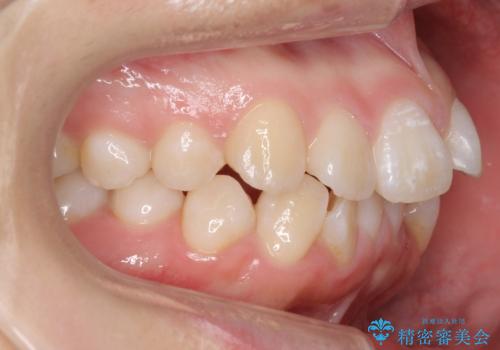

- 前歯のがたがたを主訴に来院。

口元も下げたいとのことでした。

成人式の時に前歯が下がって、揃った状態で写真を撮ることができ、大変喜んでおられました。